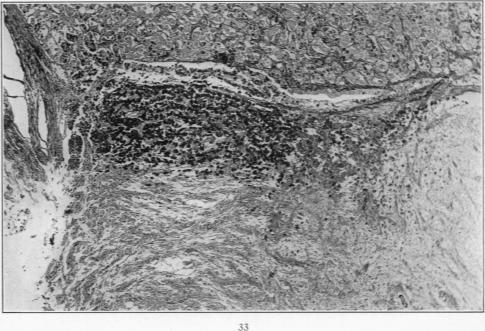

Hyperactivation of the Neurohypophysis as the Pathological Basis of Eclampsia and Other Hypertensive States.

Am J Pathol. 1934 Mar;10(2):145-176.31.

Hyperactivation of the Neurohypophysis as the Pathological Basis of Eclampsia and Other Hypertensive States.神经垂体的过度激活作为子痫及其他高血压状态的病理基础